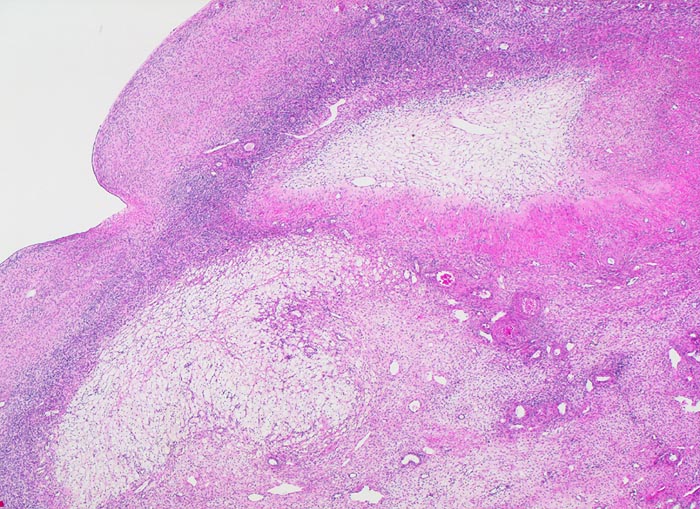

PathoPic – image database / PathoPic ID 4185 - atretischer Follikel

atretischer Follikel

Rechts oben im Bild ein atretischer Follikel: Die zentrale Zone wird durch lockeres Bindegewebe ersetzt. Die Zona pellucida (Basalmembran) ist kollabiert und ist gekräuselt und umfasst das lockere Zentrum. Degenerierendes Corpus luteum menstruationis links unten im Bild bestehend aus hellen Granulosaluteinzellen mit lipidreichem Zytoplasma und pyknotischen Kernen.

Im Verlauf des Lebens geht ein Grossteil der Primordialfollikel zu Grunde ohne eine Narbe zu hinterlassen. Eine Minderheit entwickelt sich weiter und können in jedem Stadium der Entwicklung atresieren. Nach der Atresie eines grossen Follikels kann sich eine grosse kollagene Narbe bilden, ein Corpus fibrosum, welches wie ein Corpus albicans geformt ist.